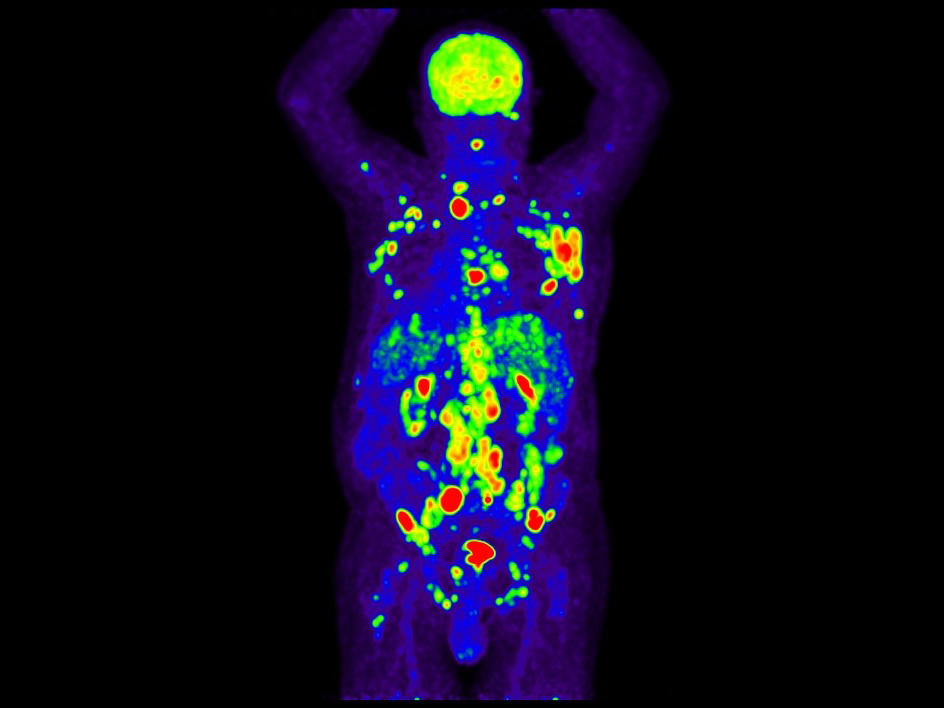

An FDG-PET scan of a man with Hodgkin lymphoma showing cancer (marked by areas of red and yellow-orange) throughout the upper body.

An imaging scan of a man with advanced Hodgkin lymphoma, showing multiple areas with cancer (red and yellow-orange) throughout the upper body.

Credit: Courtesy of Pranav Sharma, Radiopaedia.org. CC BY-NC-SA 3.0